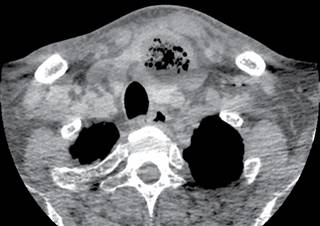

Masculino de 60 años de edad con diabetes mellitus de cinco años de evolución no controlada, sin otros antecedentes, relata presentar fiebre y faringitis de 15 días, acompañada de dolor en cuello, faringe, oído izquierdo y región retroauricular izquierda; manejado por facultativo con AINE y antibiótico no especificado, llegando el dolor a ser intolerable por lo que acude a la institución; a la exploración física: signos vitales normales, fiebre de 38.5 oC; eritema en cara anterolateral izquierda de cuello, dolor intenso en 10/10 en escala visual análoga (EVA 1-10) a la palpación de lóbulo izquierdo de tiroides, con irradiación a cara anterior de tórax, región supraclavicular y oído izquierdos; resto de exploración normal. Se ingresa, los exámenes de laboratorio mostraron: leucocitosis de 27,000/mm3 con 89% de polimorfonucleares, perfil tiroideo normal y glucosa de 320 mg/dL. Se inició antibióticos empíricos con linezolid 600 mg IV BID, meropenem 1 g IV TID, clindamicina 300 mg IV QID y control de glucosa con esquema de insulina. Se efectuó ultrasonido de cuello (Figura 1) encontrando: lesiones hiperecoicas con tendencia a la confluencia, extendidas en y alrededor del lóbulo tiroideo izquierdo. La tomografía computarizada mostró: presencia de burbujas en la glándula tiroides y a través de los tejidos blandos cervicales hacia el mediastino superior (Figuras 2 y 3). El tránsito esofágico con trago de bario no reportó presencia de fístula. A los dos días de su ingreso se encontró aumento de volumen del lóbulo izquierdo de tiroides; se efectuó punción guiada por ultrasonido, extrayendo escaso líquido seropurulento para cultivo con resultado de Staphylococcus aureus, a los seis días de hospitalización los leucocitos descendieron a 11,000/mm3. Después de 14 días de tratamiento, con mejoría clínica del dolor, de la glucemia y disminución de leucocitosis, manteniéndose el perfil tiroideo dentro de límites normales, se solicitó nueva tomografía (Figura 4) que mostró persistencia de absceso, por lo que se programó cirugía, drenando material purulento, postoperatorio sin problema; a un mes de postoperatorio, paciente asintomático, con ultrasonido de control normal al igual que perfil tiroideo.

Figura 3: Imagen de tomografía axial computarizada que demuestra colección heterogénea con líquido y gas en el lóbulo tiroides izquierdo, con desplazamientos anterior del istmo y lateral de la tráquea, asociado a aumento de volumen y densidad en los tejidos blandos del opérculo torácico.